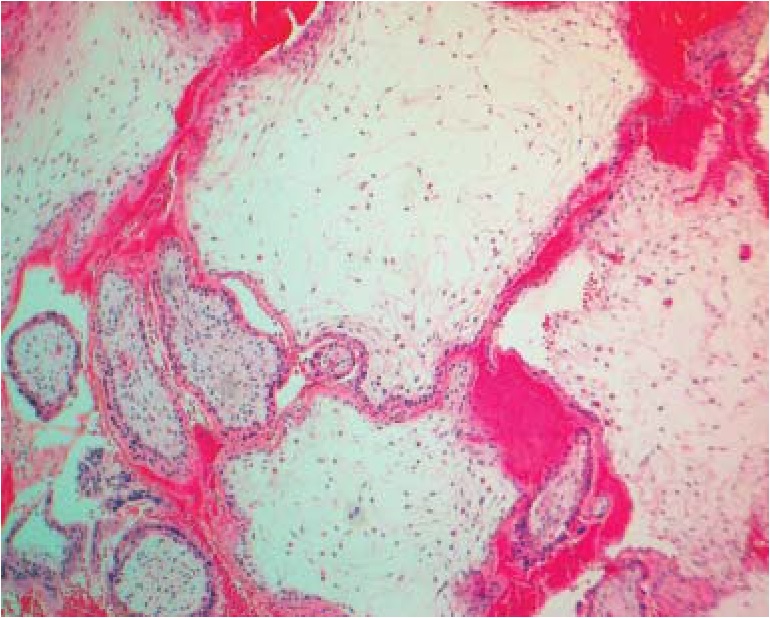

В остальной группе трисомий, в частности при трисомии по 13-й хромосоме, ведущим диагностическим признаком была выраженная гидропическая дистрофия стромы ворсин хориона с трансформацией их в крупные кистозные полости (цистерны) и полная аваскуляризация (рис. 2). Кроме того, в ряде случаев при трисомии по 13-й хромосоме отмечался выраженный фиброз ворсин хориона (рис. 3). Покровный хориальный эпителий был с резко выраженными признаками атрофии и имел вид тонкой узкой полоски. Наиболее выраженной кистозная трансформация ворсин была при трисомии по 16-й хромосоме, единичные ворсины напоминали картину, схожую с пузырным заносом.

Рис. 2. Гидропическая дистрофия ворсин хориона с транформацией в цистерны при трисомии по 13-й хромосоме. Окраска гематоксилином-эозином, ув. ×180